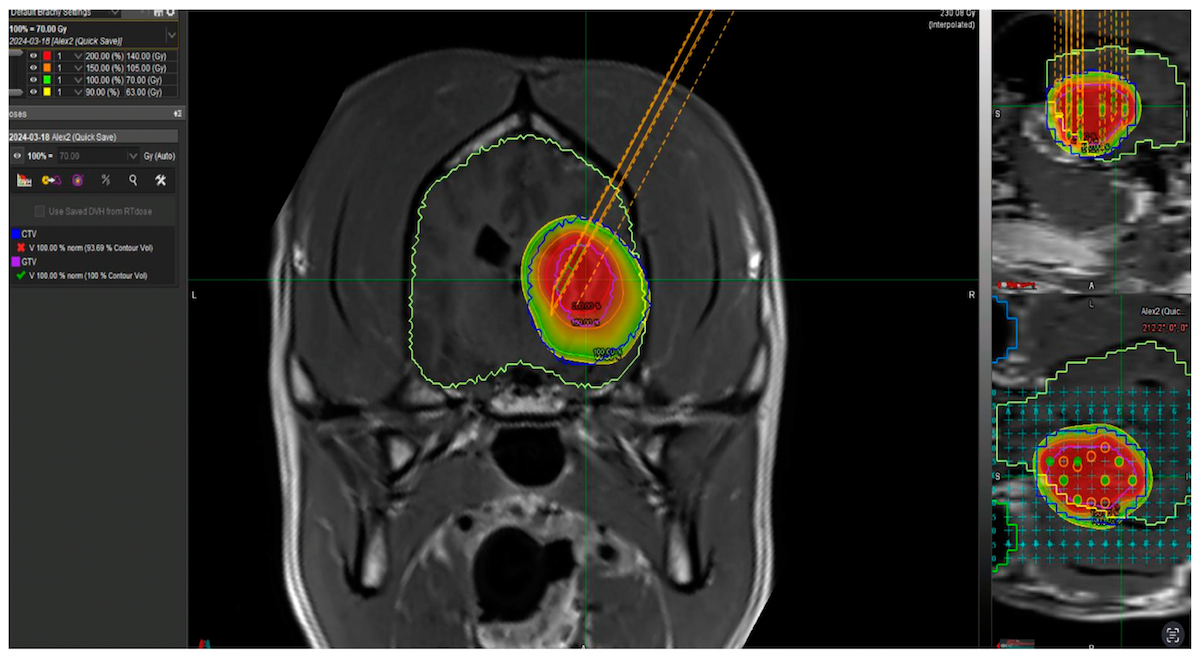

This MRI scan of a dog’s brain shows where the cesium-131 “seeds” will be placed for brachytherapy. The dog had a brain tumor removed and the cesium-131 will serve as an inner radiotherapy to deter tumor regrowth.(Image provided)

Before the dog went under surgery, an MRI scan of the dog’s brain was conducted. MRI is the “gold standard” in detecting and monitoring brain tumors because they show up better on MRI than X-ray or CT (computed tomography) scans.

After imaging revealed the location of a tumor, it was removed, and the cesium-131 were arranged in two parallel rows inside the dog’s brain near the area where the tumor was. Scarpelli said it’s common practice in human patients to use cesium-131 in an area after a tumor is surgically removed.